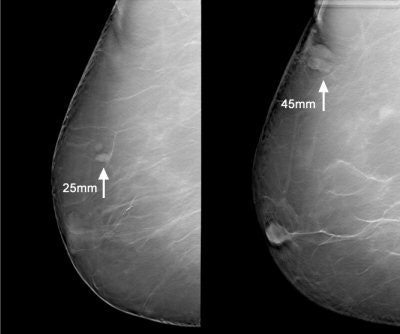

![]() |

| Above, a DBT study in CC and MLO view with a dramatic lesion. Below, DBT study in CC view with two lesions at two different levels. Images courtesy of Dr. Laurie Fajardo, Breast Imaging Research, University of Iowa, Iowa City. |